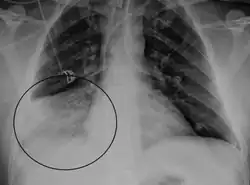

.png)